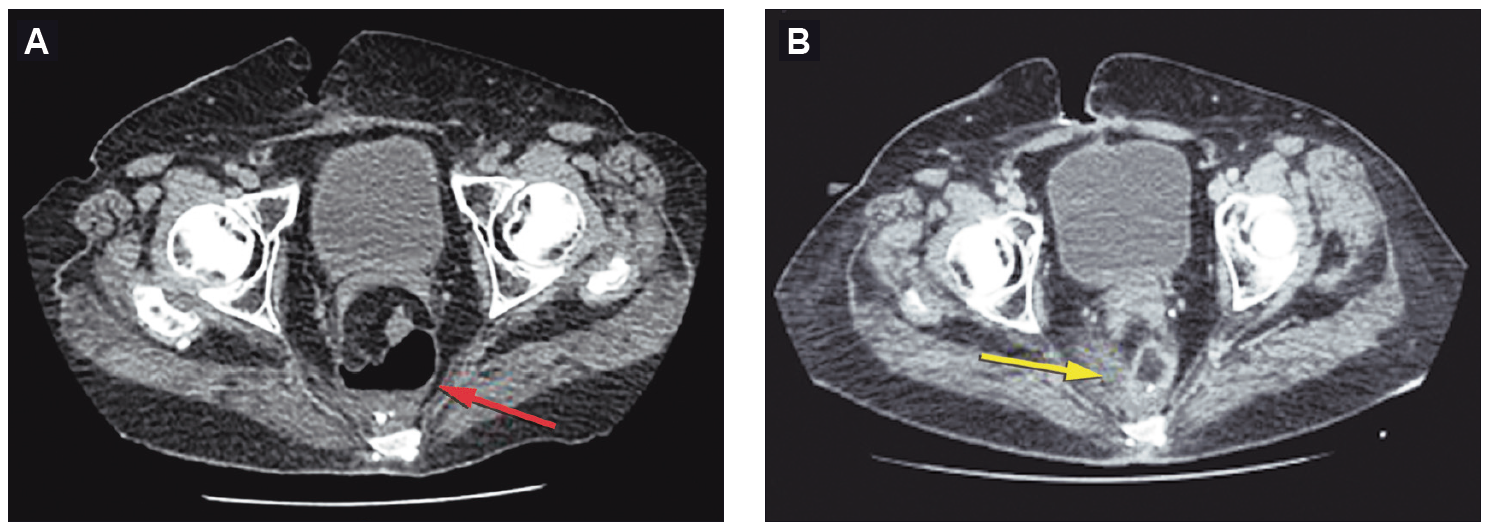

Figura 1A. Tomografía previa al tratamiento: colección pélvica retroanastomótica

presacra proximal a la anastomosis de 7 cm de diámetro con un nivel hidroaéreo (flecha roja). 1B.

Tomografía al momento de finalizar el tratamiento: obliteración de la cavidad presacra, esponja

colocada y el catéter de succión (flecha amarilla)

Se presenta el caso de una mujer de 76 años con antecedentes de obesidad y un adenocarcinoma de recto (T2N1M0) por el que se realizó neoadyuvancia con quimioradioterapia (4500cGy) y posteriormente resección anterior del recto por una remisión incompleta, con colorrecto anastomosis baja (6 cm del margen anal) y confección de ileostomía de protección. Luego del alta, al decimoquinto día postoperatorio la paciente refirió dolor abdominal y salida de secreción purulenta y fétida por el ano, por lo que se decidió volver a internarla. En el laboratorio se observó la presencia de anemia normocítica-normocrómica (Hb 10,3 g/dl), sin leucocitosis, plaquetas de 287.000 10^3/uL, tiempo de protrombina de 100%, INR 0,99, con valores de velocidad de eritrosedimentación y proteína C reactiva normales. En la TAC de abdomen y pelvis se observó un aumento de la densidad de la grasa mesentérica a nivel de la región del flanco izquierdo y adyacente al colon descendente, huellas quirúrgicas y, a nivel rectal, una imagen con nivel hidroaéreo contigua a la anastomosis (Figura 1A). La videorectosigmoidoscopía confirmó la presencia de una anastomosis permeable con una dehiscencia del 50% de la circunferencia y una longitud en su eje mayor de 80 mm (Figura 2). Se consideraron diferentes posibilidades terapéuticas, incluyendo el desmantelamiento de la anastomosis, el drenaje transanal con tubo anastomótico, el drenaje percutáneo y los procedimientos endoscópicos avanzados como la colocación de stents, clips o la terapia endoluminal asistida por vacío. Priorizando la preservación de la anastomosis, dado que la paciente no presentaba peritonitis, sepsis o falla multiorgánica, se optó por un tratamiento mínimamente invasivo tipo VAC, tras evaluar los costos, riesgos, beneficios y comorbilidades de la paciente. Por vía endoscópica, se colocó en la cavidad posterior a la dehiscencia un catéter con una esponja de poliuretano en su extremo, conectado a sistema de aspiración negativa continua a 150 mm Hg (Figura 3). Se realizaron sesiones de lavado y de recambio del drenaje y esponja cada 72 horas, requiriendo 3 recambios hasta obtener la obliteración de la cavidad con tejido de granulación. Al realizar el control tomográfico se observó la obliteración de la cavidad presacra, la esponja colocada y el catéter de succión (Figura 1B). Luego de ese último recambio se retiró de manera definitiva el sistema VAC (Figura 4). La paciente presentó una adecuada recuperación y se le otorgó el alta hospitalaria a las 48 horas de haber retirado el sistema VAC. A los tres meses se realizó un control endoscópico en el que se observó la permeabilidad de la anastomosis y la resolución completa de la dehiscencia (Figura 5) y a posteriori se realizó el cierre de la ileostomía de protección.